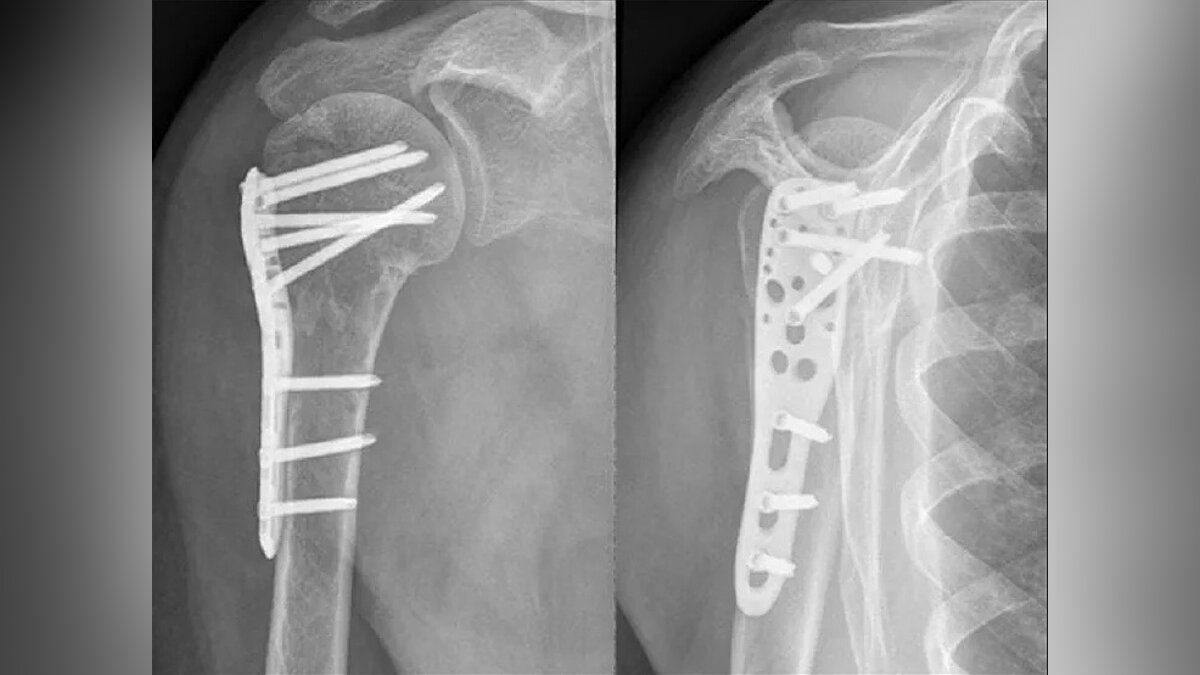

Медицинские снимки: Пластина в левом предплечье